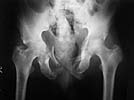

65 year old male patient was allegedly injured in a railway accident two months ago. He was treated till recently elswhere and has now been transferred to our centre. Had suffered pelvic ring injury and urinary bladder injury. Was treated with lower abdominal laparotomy, bladder repair and an SPC. No active treatment was done for the bony injuries.

In our centre we found that there is an unstable pelvis which could be compressed and distracted. bilateral acetabular injury with central fracture on the right side - femoral head partially caught in the floor of acetabulum, left side femoral head located, sacral fracture with ant body comminution etc, a suprapubic urinary catheter with wound infection, a bed sore over the left gluteal region etc. Our urologist was able to convert the bladder drainage to an urethral catheter. The right femoral head could be pulled out of the floor of the acetabulum and reduction retained on axial skeletal traction. The anterior pelvic ring has been stabilised on external fixator. Small rotation flap was done for the left gluteal pressure sore and is healing.

I think your plan is okay. His femoral head damage looks horrible in the film you attached. He's likely to develop arthritis in the future - you may be smart to avoid hardware and surgery with a hip like that.